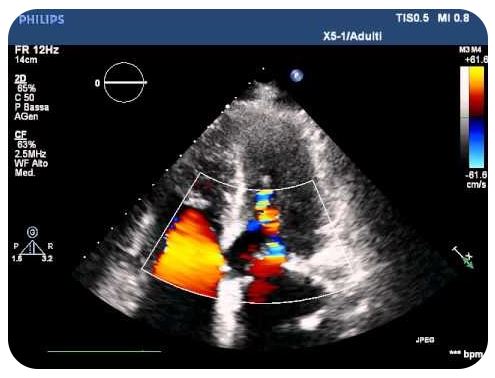

Ecocardiocolordoppler

Un ecocardiogramma può salvare la vita. Attraverso le onde sonore è in grado di riprodurre su uno schermo le immagini del cuore in movimento, durante il suo battito, per verificare se vi sono anomalie del muscolo cardiaco o delle valvole, oppure dei grandi vasi sanguigni, come l’aorta che ad esempio può essere soggetta ad aneurisma, senza provocare sintomi precoci.

IN PARTICOLARE, CON L’ECOCOLORDOPPER CARDIACO A RIPOSO È POSSIBILE ESEGUIRE:

la valutazione qualitativa e quantitativa delle malattie delle valvole cardiache

la valutazione delle dimensioni e del movimento delle pareti del cuore

la valutazione delle cardiopatie congenite

la valutazione degli esiti di un intervento cardiochirurgico.